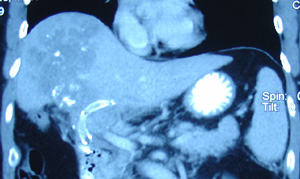

CT Scan Report: 3 October 2008: There is ill-defined hypodense lesion at Segment VI. It measures 3.5 x 3.5 cm. Feature is suggestive of right lobe hepatoma.

A CT scan done of 10 February 2009 indicated:

- Worsening of the liver with increase in the number and size of the liver nodules.

- There was thrombosis of the adjacent portal vein extending partially to the main portal vein.